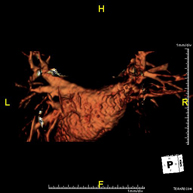

- Angio-RM intracraneal

Prueba diagnóstica no invasiva que consiste en la obtención de imágenes de alta definición anatómica de las arterias cerebrales mediante el empleo de un campo electromagnético y ondas de radio (con un emisor y un receptor). No utiliza radiación ionizante. En la mayoría de los casos es necesario el empleo de contraste paramagnético (Gadolinio). Permite un estudio angiográfico no invasivo gracias a la inyección de Gadolinio con posterior reconstrucción en 2D y 3D, gracias a estaciones de trabajo especializadas. Indicaciones: malformaciones vasculares, aneurismas de arterias cerebrales, arteriosclerosis.

- Angio-RM Troncos supraaórticos

Prueba diagnóstica no invasiva que consiste en la obtención de imágenes de alta definición anatómica de las arterias carótidas y vertebrales a nivel de cuello, mediante el empleo de un campo electromagnético y ondas de radio (con un emisor y un receptor). No utiliza radiación ionizante. En la mayoría de los casos es necesario el empleo de contraste paramagnético (Gadolinio). Permite un estudio angiográfico no invasivo gracias a la inyección de Gadolinio con posterior reconstrucción en 2D y 3D, gracias a estaciones de trabajo especializadas. Indicaciones: Problemas circulatorios cerebrales, síncope.